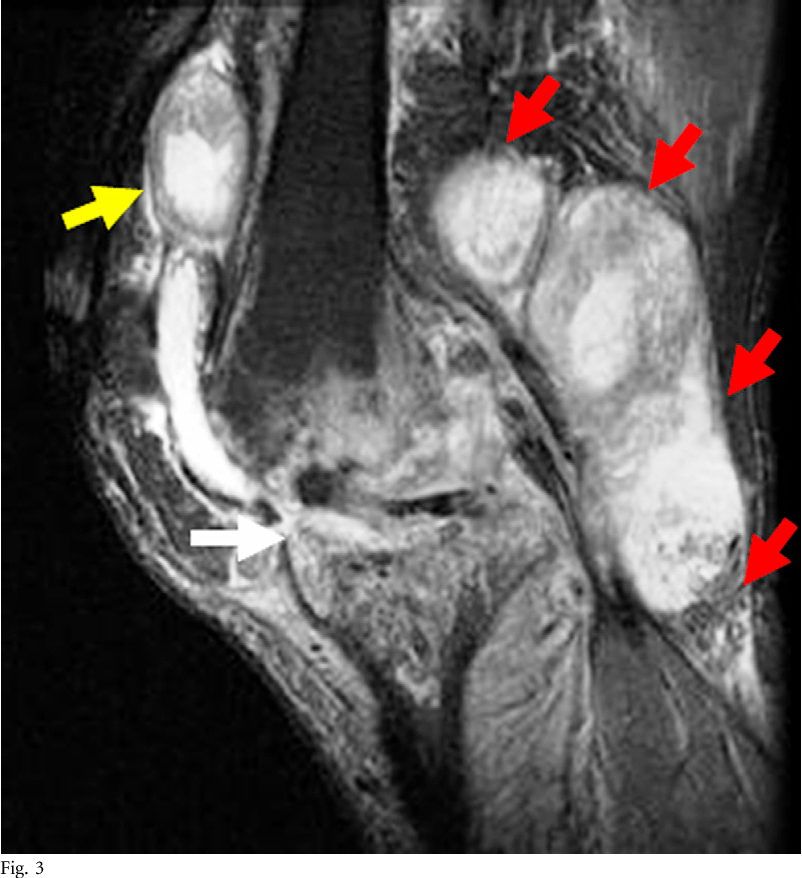

Tuberculous arthritis in a 45yearold male. Coronal T1weighted Tuberculous Arthritis Def It results from the contiguous involvement of the underlying skin of other tuberculous foci, and commonly of tuberculosis lymphadenitis, bone. Through the blood and lymphatic. Tuberculous arthritis of the ankle can lead to degenerative changes in the bone and articular cartilage and even to joint collapse. Tuberculous arthritis is the second most common musculoskeletal tb infection.20,54,55,61,62 of the extrapulmonary forms. Tuberculous Arthritis Def.